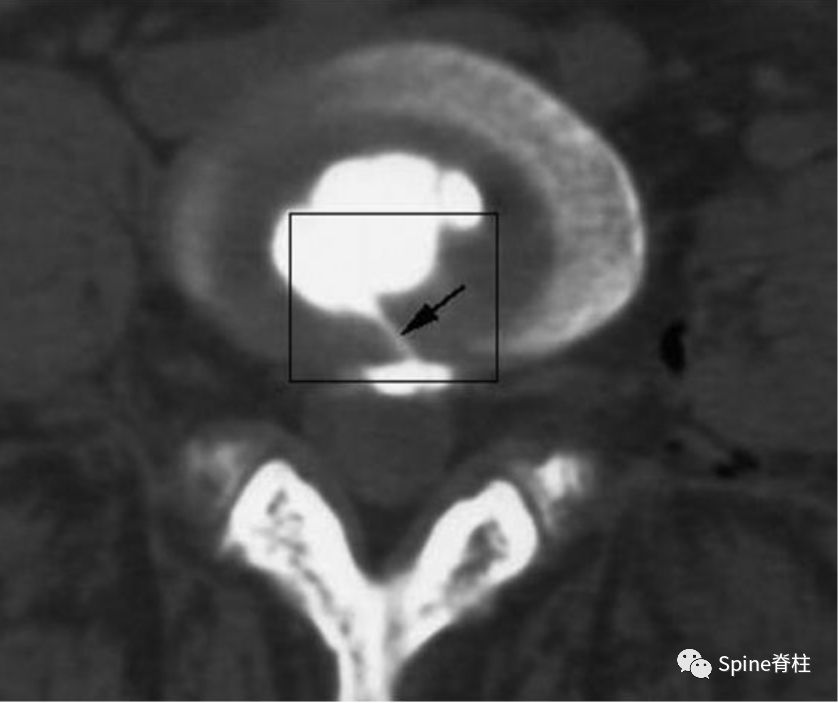

“黑椎间盘”是不是疼痛的?通常需要椎间盘造影或阻滞来明确或排除。虽有争议,目前腰椎间盘造影术仍是诊断椎间盘源性腰痛的“金标准”。椎间盘造影诱发平时疼痛是明确疼痛椎间盘的有效方法,或者椎间盘内注射*醉药麻**(比如布比卡因)后平时的腰痛症状明显消失。疼痛的椎间盘在造影剂注射过程中,造影剂要么通过放射状纤维环撕裂流向椎间盘外方,要么通过放射状终板撕裂流向椎体,两者都诱发患者平时的腰痛反应。这也是鉴别终板源性腰痛和由纤维环撕裂引起的椎间盘源性腰痛的主要手段。

图:椎间盘造影时,造影剂流至破损的终板